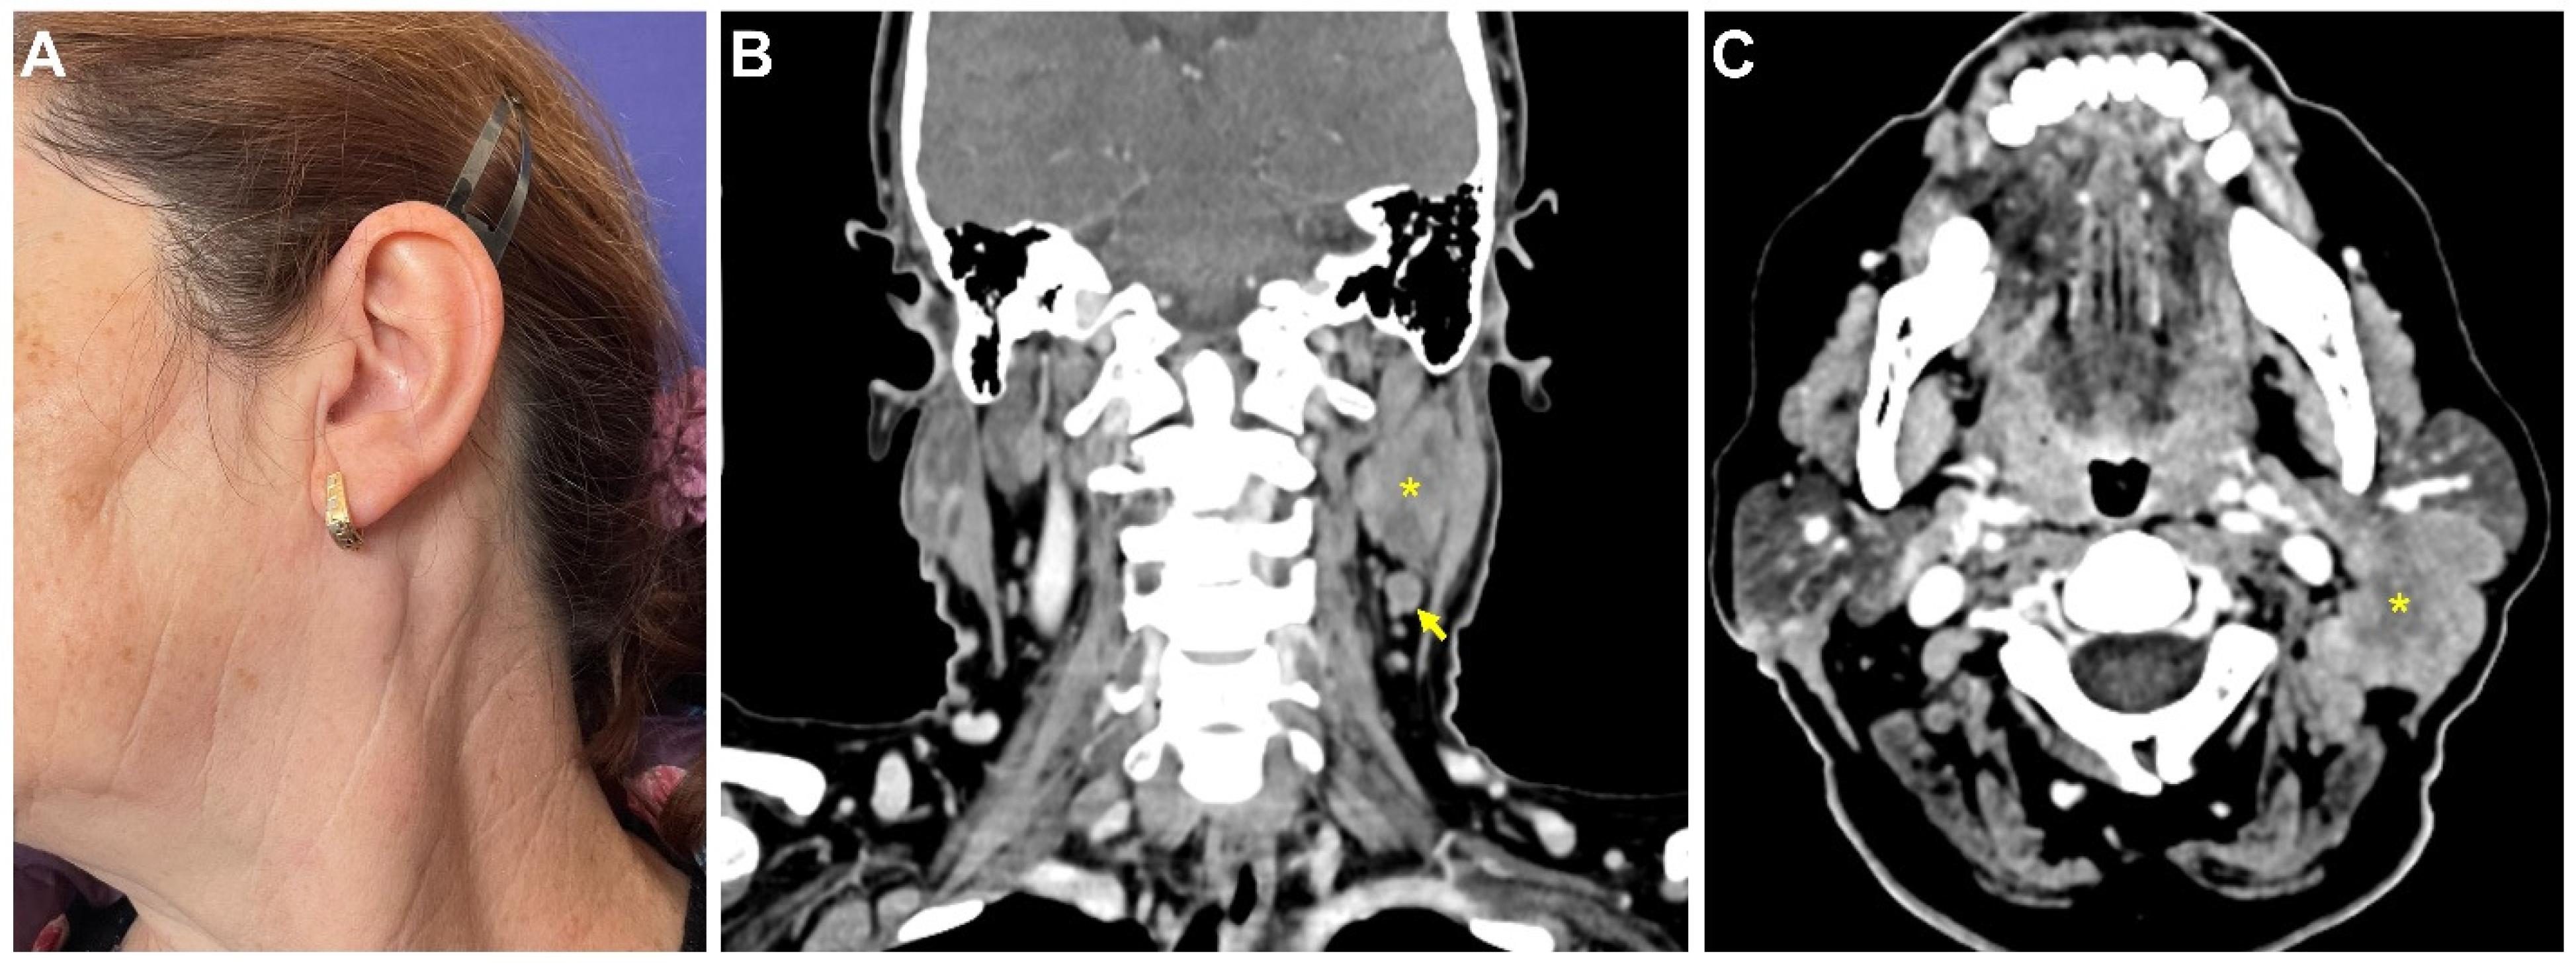

CASE 1: In October 2021, a 58-year-old female patient was referred to the Department of Oral and Maxillofacial Surgery of the “Carol Davila” Central University Emergency Military Hospital, with complaints of a painful round mass in the upper left cervical area. Clinical examination revealed a tumor mass at the angle of the left parotid gland, firm and painful on palpation, fixed on the underlying tissue, with a diameter of approximately 4 cm (Figure 1A). The patient was recently vaccinated for protection against COVID-19 infection, with a two-regimen mRNA vaccine (Pfizer-BioNTech)—the first dose on 22 May 2021 and the second dose on 12 June 2021. The patient reported that one week after the second dose inoculation, she noticed the sudden development of this painful cervical mass, which was small at the beginning and was associated with a flu-like syndrome: sore throat, odynophagia, headache, and rhinorrhea. The patient took over-the-counter anti-inflammatory drugs, with complete resolution of the flu-like symptoms within a week, except for the cervical mass, which continued to grow slowly.

Figure 1.

Clinical and imaging aspects at presentation. Clinical aspect (A). Contrast-enhanced CT scan of the neck in the coronal (B) and axial (C) planes. Large necrotic tumor (*) located on the posterior and inferior aspect of the left parotid gland, with infiltration of the adjacent muscles and enlarged regional lymph nodes (arrow).

Cervical ultrasonography, recorded one month before presentation (in September 2021), objectified a well-defined, heterogeneous hypo- and hyperechoic nodular mass, located in the upper left cervical region, measuring 35.5/20/26 mm. The lesion was in direct contact with the posterior contour of the parotid gland and had a weak Doppler signal in the periphery, suggestive of a benign tumor. Several reactive lymph nodes with a maximum diameter of 17.6/8.3 mm were found adjacent to the inferior contour of the lesion. The contrast CT scan revealed a tumor mass located at the posteroinferior parotid gland contour, with irregular margins, measuring 38/26/32 mm with posterior infiltration into the paravertebral muscles and necrotic areas within the lesion, suggestive of malignancy (Figure 1B,C). Multiple lymph nodes in levels IIA and IB with a maximum diameter of 8 mm were described. There were no other abnormal findings.